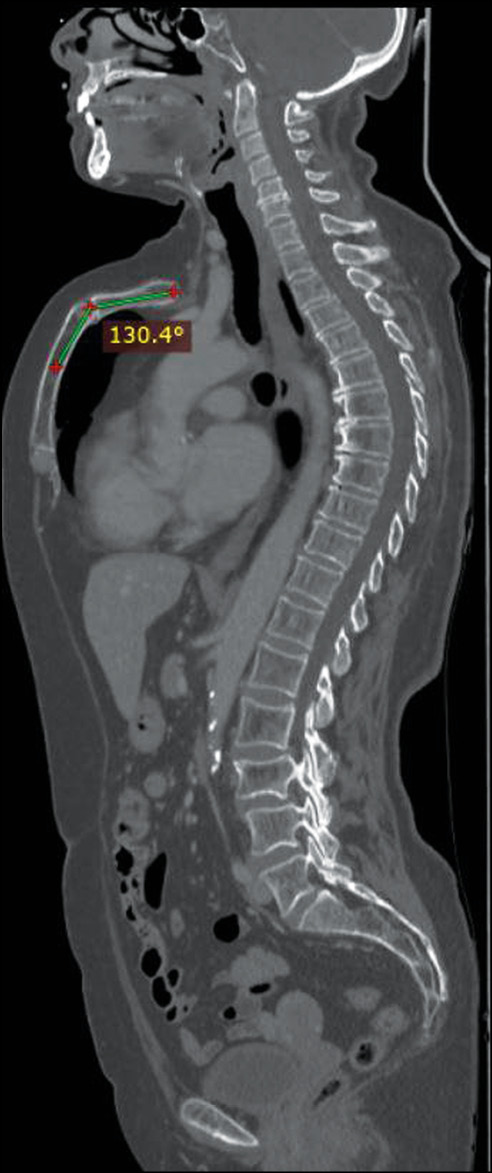

В статье представлен случай 66-летней пациентки, обратившейся в клинику для прохождения повторной компьютерной томографии после операции и химиотерапии по поводу рака молочной железы, с жалобами на частые ежегодные эпизоды одышки, кашля, бронхита, более выраженные в детстве. Результаты компьютерной томографии показали отсутствие метастатических поражений и других сопутствующих заболеваний, за исключением редкой формы деформации передней грудной стенки, так называемой килевидной деформации верхней части грудной клетки (pectus carinatum ― верхний киль) по хондроманубриальному типу. Угол в дорсальном направлении составлял 130º, длина грудины 9 см без вдавления в нижней трети.